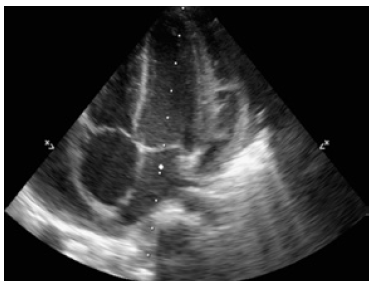

Studies to rule out immunological involvement were within normal limits (Table 1). Given the cyclic and echocardiographic improvement, discharge was authorized (Figure 4).